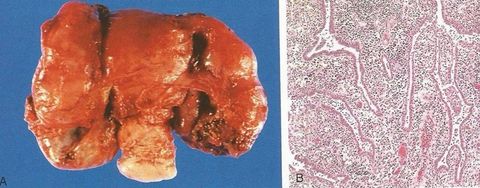

DIAGNÓSTICO. Qual é a etiologia dessa alteração? Leiomioma intramural. Mutação monoclonal.